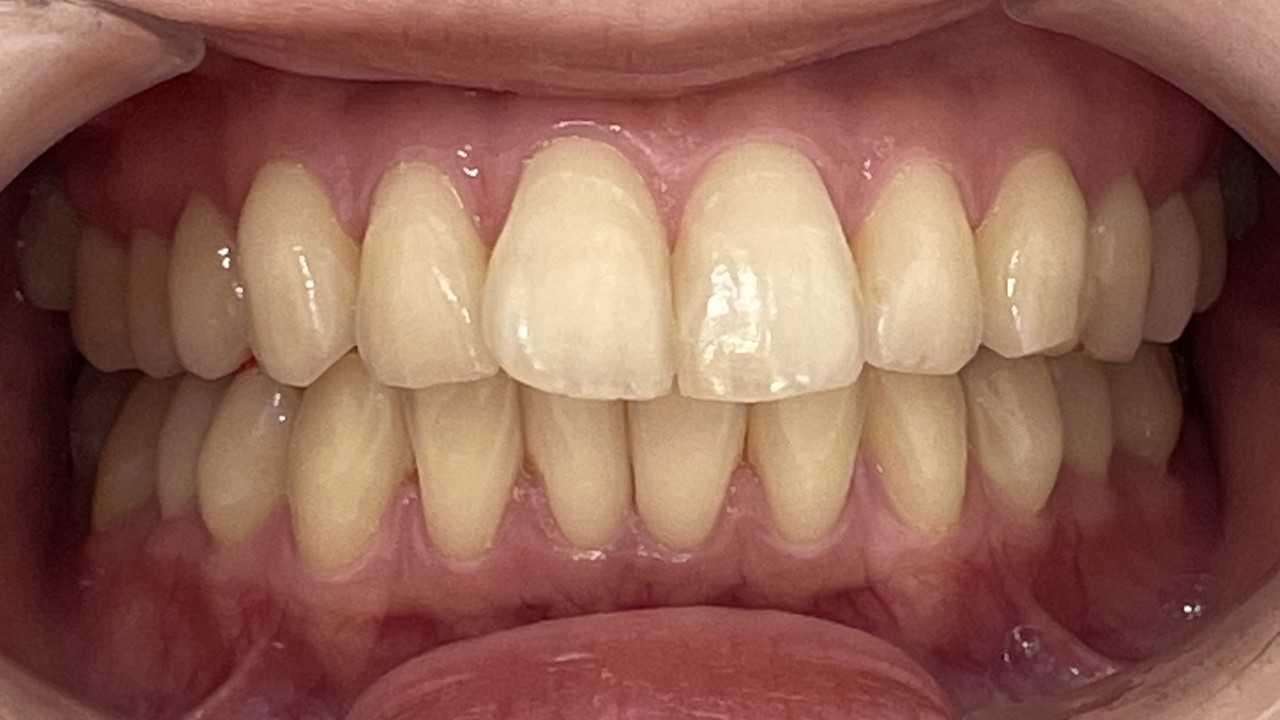

Before

After

矯正の種類 / invisalign GO

年齢・性別 / 40代女性

主訴  /  上下の叢生、開咬、オーバージェット

治療期間 / 12ヶ月

費用 / 簡易検査 5,000円(税別) 精密検査 30,000円(税別)

両額マウスピース 450,000円(税別) 両額リテイナー料 40,000円(税別)

※マウスピース交換時別途調節料5,000円(税別)

副作用 / 口内炎・歯の移動に伴う痛み・知覚過敏 ※数日で収まる場合が多いです

リスク / 後戻り防止の為、夜のみマウスピースで保定を指示